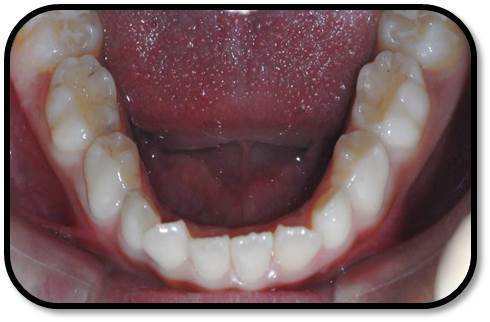

儿童7岁半,男 主诉:右上前牙自发痛,咬合痛3天。 现病史:患儿右上前牙自发痛,咬合痛3天,牙龈肿痛1天,今来诊求治。否认前牙外伤史。 既往史,家族史:无特殊 全身情况:健康